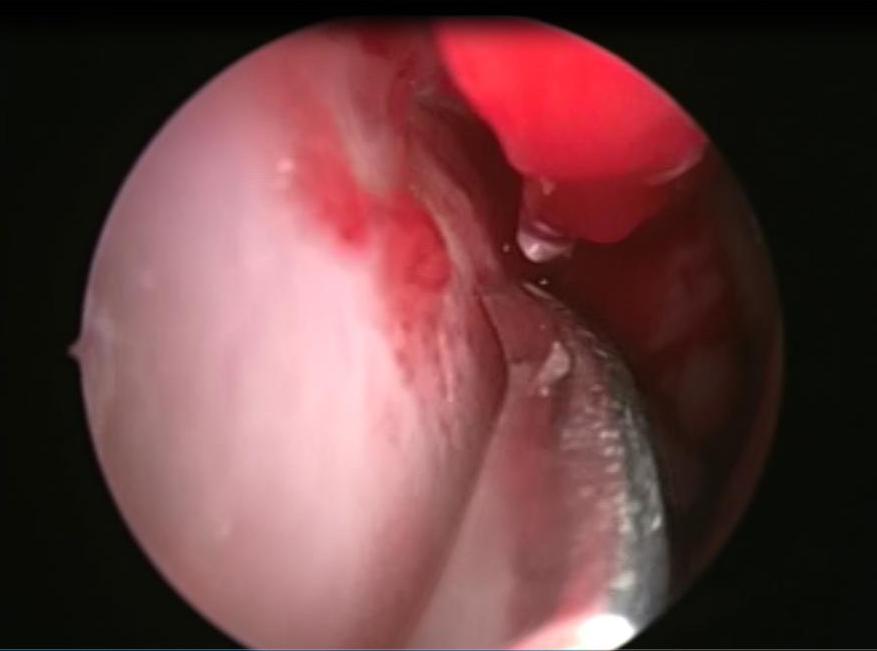

It is an autosomal dominant vascular disorder, which has a variety of clinical manifestations, with epistaxis being one of the most common. Many treatment options exist for epistaxis, but with no consensus on which is the method of choice. We describe the case of a patient with hereditary hemorrhagic telangiectasia (HHT) secondary epistaxis with septoplasty managed with synthetic hard graft, which improved intensity and frequency of bleeding episodes. This technique is a variant of the septodermoplasty described by several authors, but the use of synthetic dura can help in obtaining better results and avoid taking skin grafts from other sites different from the surgical site.